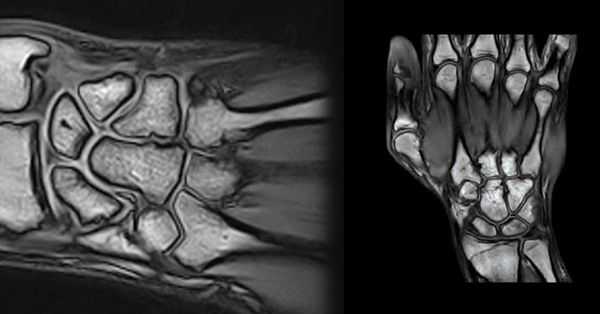

Патология костей

МРТ визуализирует переломы, трещины костей, остеопороз (снижение плотности костной ткани), остеомиелит (гнойное воспаление). Можно оценить качество костной мозоли после перелома. Диагностировать асептический некроз запястных костей - ладьевидной, полулунной (болезнь Кинбека). Увидеть анкилоз сустава - полное сращение костей в суставе в результате артроза.

От точного совмещения всех структур зависит функция руки в будущем. На рентгенограмме хорошо видны кости. Можно выявить перелом, вывих, подвывих.